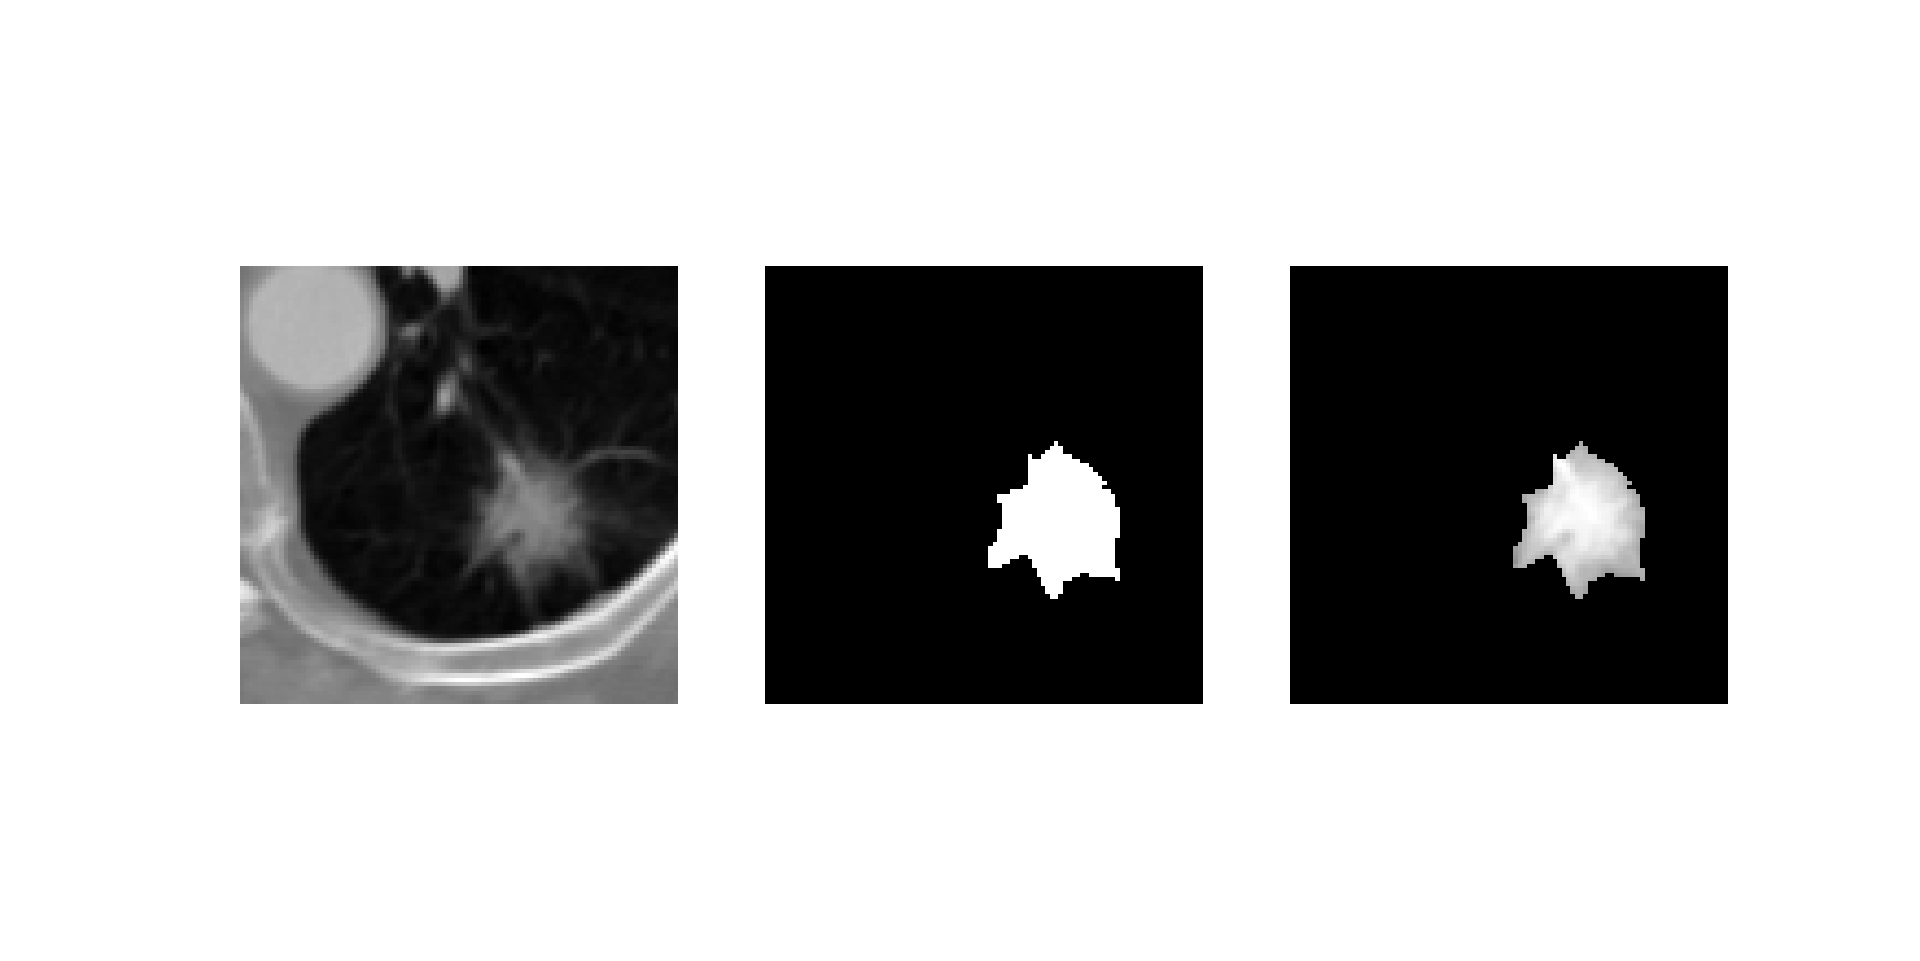

背景:我想把肺部CT图像数据和对应的掩码标签重合显示,也就是下图这种效果,通过对应元素相乘实现,但是两张图像的数据格式和分布都不相同,因此用到了normalization。

这样两张图像的像素值都在[0,1]区间内了,相乘就可以得到合成图:

img_overlap = image * mask

fig,ax = plt.subplots(1,3,figsize=[8,8])

ax[0].imshow(image[310:410,250:350],cmap='gray')

ax[1].imshow(mk[310:410,250:350],cmap='gray')

ax[2].imshow(img_overlap[310:410,250:350],cmap='gray')

for x in ax.ravel():

x.axis("off")

plt.show()